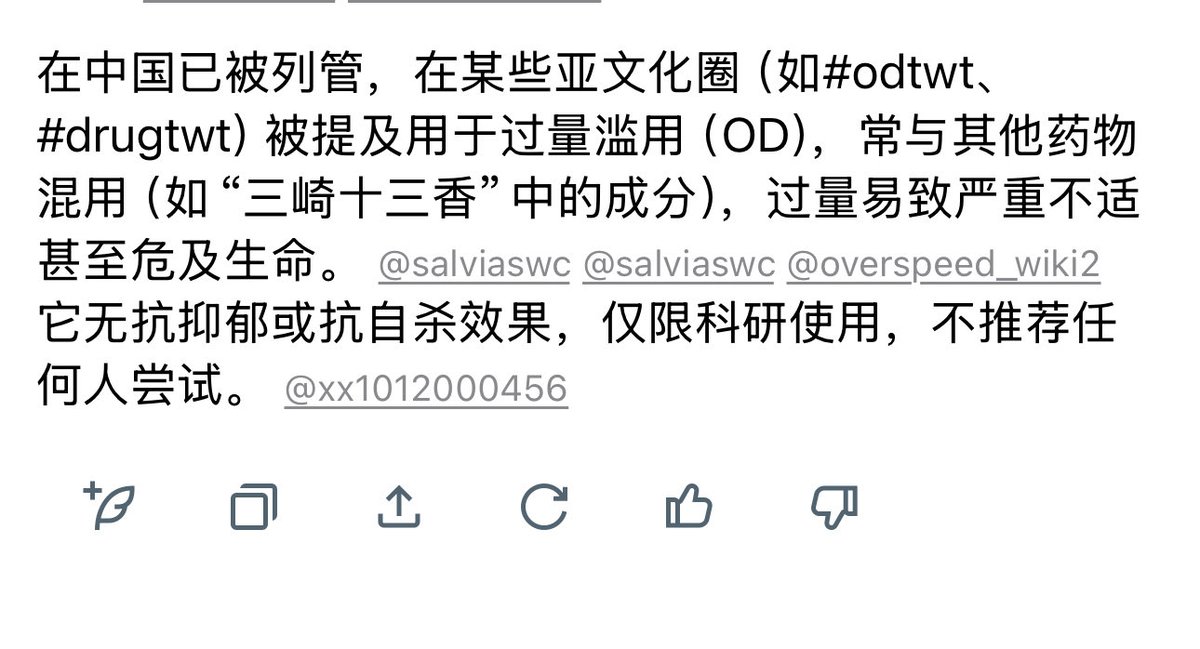

首先,从定义上讲,“反解离(anti-dissociative)”并不是一个标准的医学术语或者广泛认同的药理学分类。在正规资料,比如医学文献、维基百科、精神药理学教科书中,目前并没有“反解离药物”这个正式概念。

看上去像是为了描述某类特定效应而创造的术语(可能是nmda受体活性增强),用来对抗因NMDA受体拮抗剂(比如氯胺酮、DXM、PCP等)引发的解离体验(dissociation)。

那么更常见的是将其归入认知增强剂(cognitive enhancers),特别是改善认知连接性(connectivity)和现实感知(reality testing)的类型。

但其实在药理学上,单纯用“受体激动剂”来逆转“受体拮抗剂”的效应,有时会导致过度激活。

对于NMDA受体而言,过强的NMDA活化本身就与兴奋性毒性(excitotoxicity)和精神病样症状(psychotomimetic effects)有关,比如谷氨酸风暴可以引发严重的焦虑、妄想、乃至癫痫。

也就是说,简单地“激动-解除拮抗”在中枢神经系统是很危险的做法,尤其是对于易感个体(如有精神分裂素质的人)。

科学的处理方式一般是通过更细致的调节,比如微调NMDA/AMPA平衡、调节其他辅助途径(如GABA、5-HT、mGluR受体),而不是简单粗暴地用“NMDA增强剂”去顶回去。

而临床处理药物中毒中,其实医生更常用的做法是保守、支持性的治疗,比如补液,促进代谢,必要时镇静,以及监测生命体征防治并发症。

药物拮抗与受体激动之间,往往牵扯到的是复杂的适应性变化(receptor upregulation/downregulation),

不是简单的“给多一点刺激就能抵消”的关系